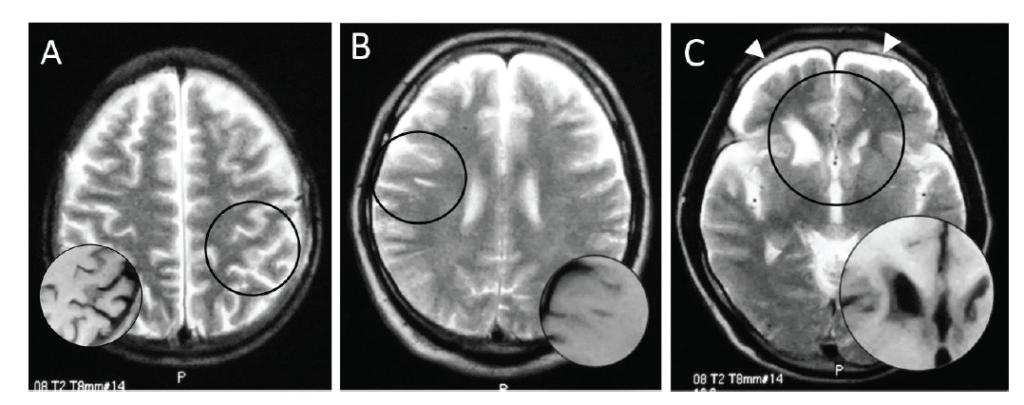

Magnetic resonance images of brains of three Ama divers: hyperintense area on T2-weighted image (circle), corresponding to hypointensity on T1-weighted image (inset). A patchy shadow in the left parietal cortex (A, No. 2), a linear subcortical lesion in the right frontal lobe (B, No. 5), and deformity of bilateral caudate heads and subdural fluid collection (allow heads) (C, No. 11).